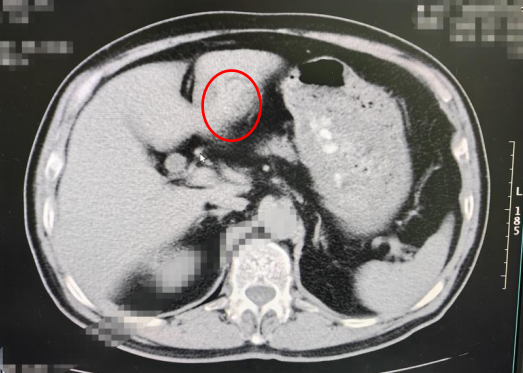

这张是未禁食的图像,可以看到红圈圈里到影像是模模糊糊,分不清哪里是胃壁,哪里是胃内容物,这种时候容易漏诊和误诊有关胃这方面的病变。 左:为饮水不足,右:为足量饮水